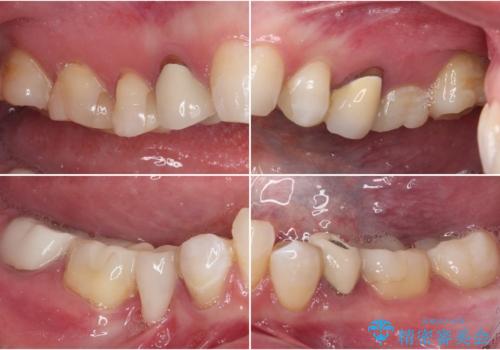

- クラウンから金属の土台が見えてきてしまったとのことで、作り替えを希望して来院された患者様です。

前歯や金属が露出している歯、痛みを感じる歯を中心に、オールセラミッククラウンにて補綴治療することとしました。

以前はセラミッククラウンのフレームとして金属が使用されており、歯肉の経年変化やセラミックのすり減りなどにより、金属が見えるようになってくることがあります。